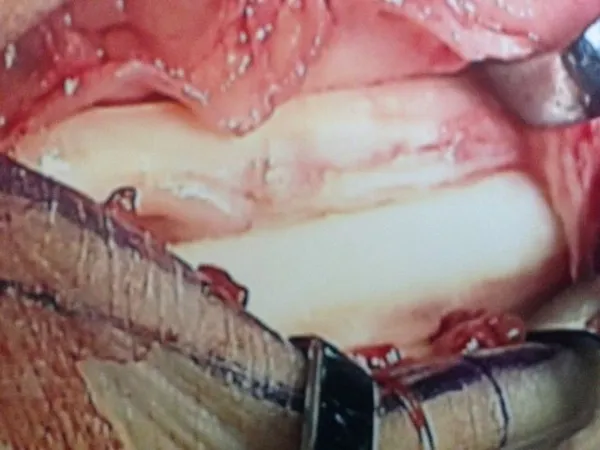

Below, Peroneal Tear with Low lying muscle belly. The muscle belly is removed and bulked to allow gliding and reduce congestion.

The muscle belly is seen at the right and closure of the sheath on the left and bottom pics.